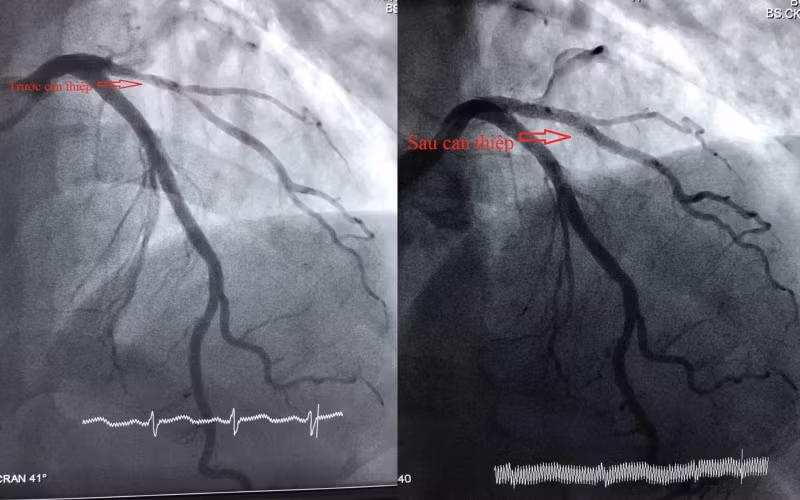

Qua khám, xét nghiệm và chụp mạch vành xác định, động mạch liên thất trước (LAD) bệnh nhân bị thâm nhiễm, hẹp 80-90% nhánh chéo 1. Bệnh nhân có chỉ định can thiệp mạch vành cấp cứu. Các bác sĩ tiến hành can thiệp mạch vành cho bệnh nhân bằng cách nong bóng và đặt stent phủ thuốc trong thời gian 30 phút.

Sau can thiệp, bệnh nhân tỉnh, mạch, huyết áp ổn định, giảm đau ngực nhiều và tiếp tục điều trị tại Khoa Tim mạch can thiệp.